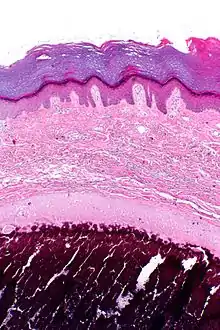

| Micrograph of calcinosis cutis. The calcification is purple (bottom of image). H&E stain. | |

Calcinosis cutis is a type of calcinosis wherein calcium deposits form in the skin. A variety of factors can result in this condition. The most common source is dystrophic calcification, which occurs in soft tissue as a response to injury. In addition, calcinosis is seen in Limited Cutaneous Systemic Sclerosis, also known as CREST syndrome (the "C" in CREST).[1] In dogs, calcinosis cutis is found in young, large breed dogs and is thought to occur after a traumatic injury.